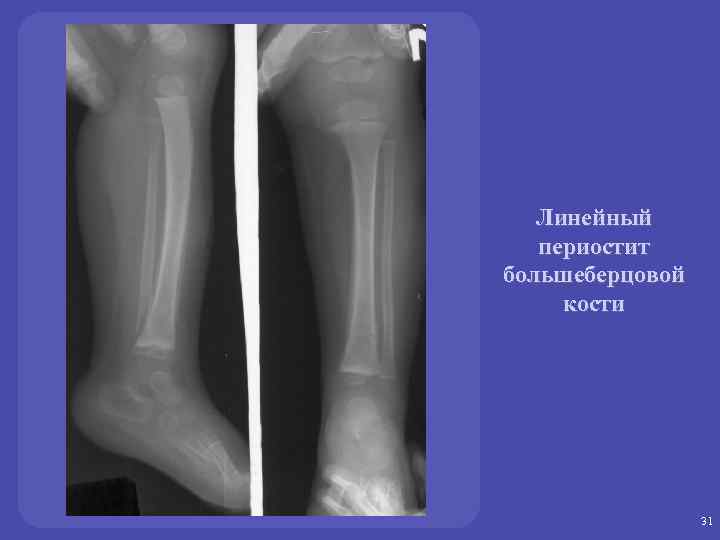

Периостит - реакция (обызвествление) надкостницы на воспалительный, опухолевый процесс или травму

Виды периостита: - линейный - слоистый - бахромчатый - кружевной - игольчатый (спикулообразный) Линейный, бахромчатый, кружевной – характерны для воспалительных заболеваний скелета Слоистый - характерен как для воспалительных, так и для онкологических процессов Игольчатый или спикулообразный – характерен только для онкологических процессов

РЕНТГЕНОЛОГИЧЕСКАЯ СЕМИОТИКА ОСТЕОМИЕЛИТА - Периостит (линейный, слоистый) - Деструкция в сочетании с репаративными процессами - Секвестр - Гиперостоз - Остеосклероз 30

Линейный периостит большеберцовой кости 31